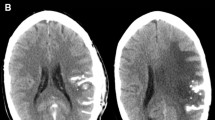

The primary endpoint of this trial was to determine the safety of this combined treatment. Clinical symptoms and laboratory data were evaluated in accordance with the Common Terminology Criteria for Adverse Events (CTCAE v3.0) [29]. Blood and urine samples were collected before and after PBT, after the 3rd CalTUMP injection, 2 weeks later, and then every 2 months thereafter. Complete blood counts, serum levels of c-reactive protein (CRP), and urinalyses were followed. Tumor markers including lens culinaris agglutinin-reactive fraction of alpha-fetoprotein (AFP-L3 fraction), protein induced by vitamin K absence or antagonist (PIVKA)-II, carcinoembryonic antigen (CEA), pancreatic cancer associated antigen (DUPAN-2), carbohydrate antigen (CA) 19–9 were monitored, and ultrasounds were taken at these sampling points. Computed tomography (CT) of the lung and abdomen was conducted to exclude possible embolic or hemorrhagic complications on the day following the third CalTUMP injection. Tumor size was evaluated in accordance with the Response Evaluation Criteria in Solid Tumors (RECIST) guidelines [31].